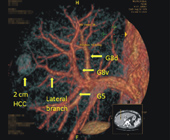

然而要精準地將想要的門靜脈分枝染上ICG非常困難。傳統上是在術中超音波定位下,進行門靜脈穿刺,但往往血管分枝太細而不易成功。而且如果沒有術前影像立體重組 (如圖二) ,外科醫師也很難確定該染哪一枝門靜脈分枝?因此要使用ICG正染法螢光導引進行微創精準肝切除,即使是最熟練的團隊也大概只有一半的成功率。本院微創肝臟手術團隊和影像醫學部黃俊傑醫師整合院內資源,利用院內多功能的整合式開刀房(Hybrid OR),不僅可以用血管攝影的技巧,精準標定需要切除的肝段,更首創術中電腦斷層確認切除範圍。確保足夠之切除邊界。李先生的3D立體微創肝癌切除更是以這種技術完成,真正體現了科技提昇人眼和人腦的極限,開啟了外科手術的新境界。

圖二、術前3D立體影像重組